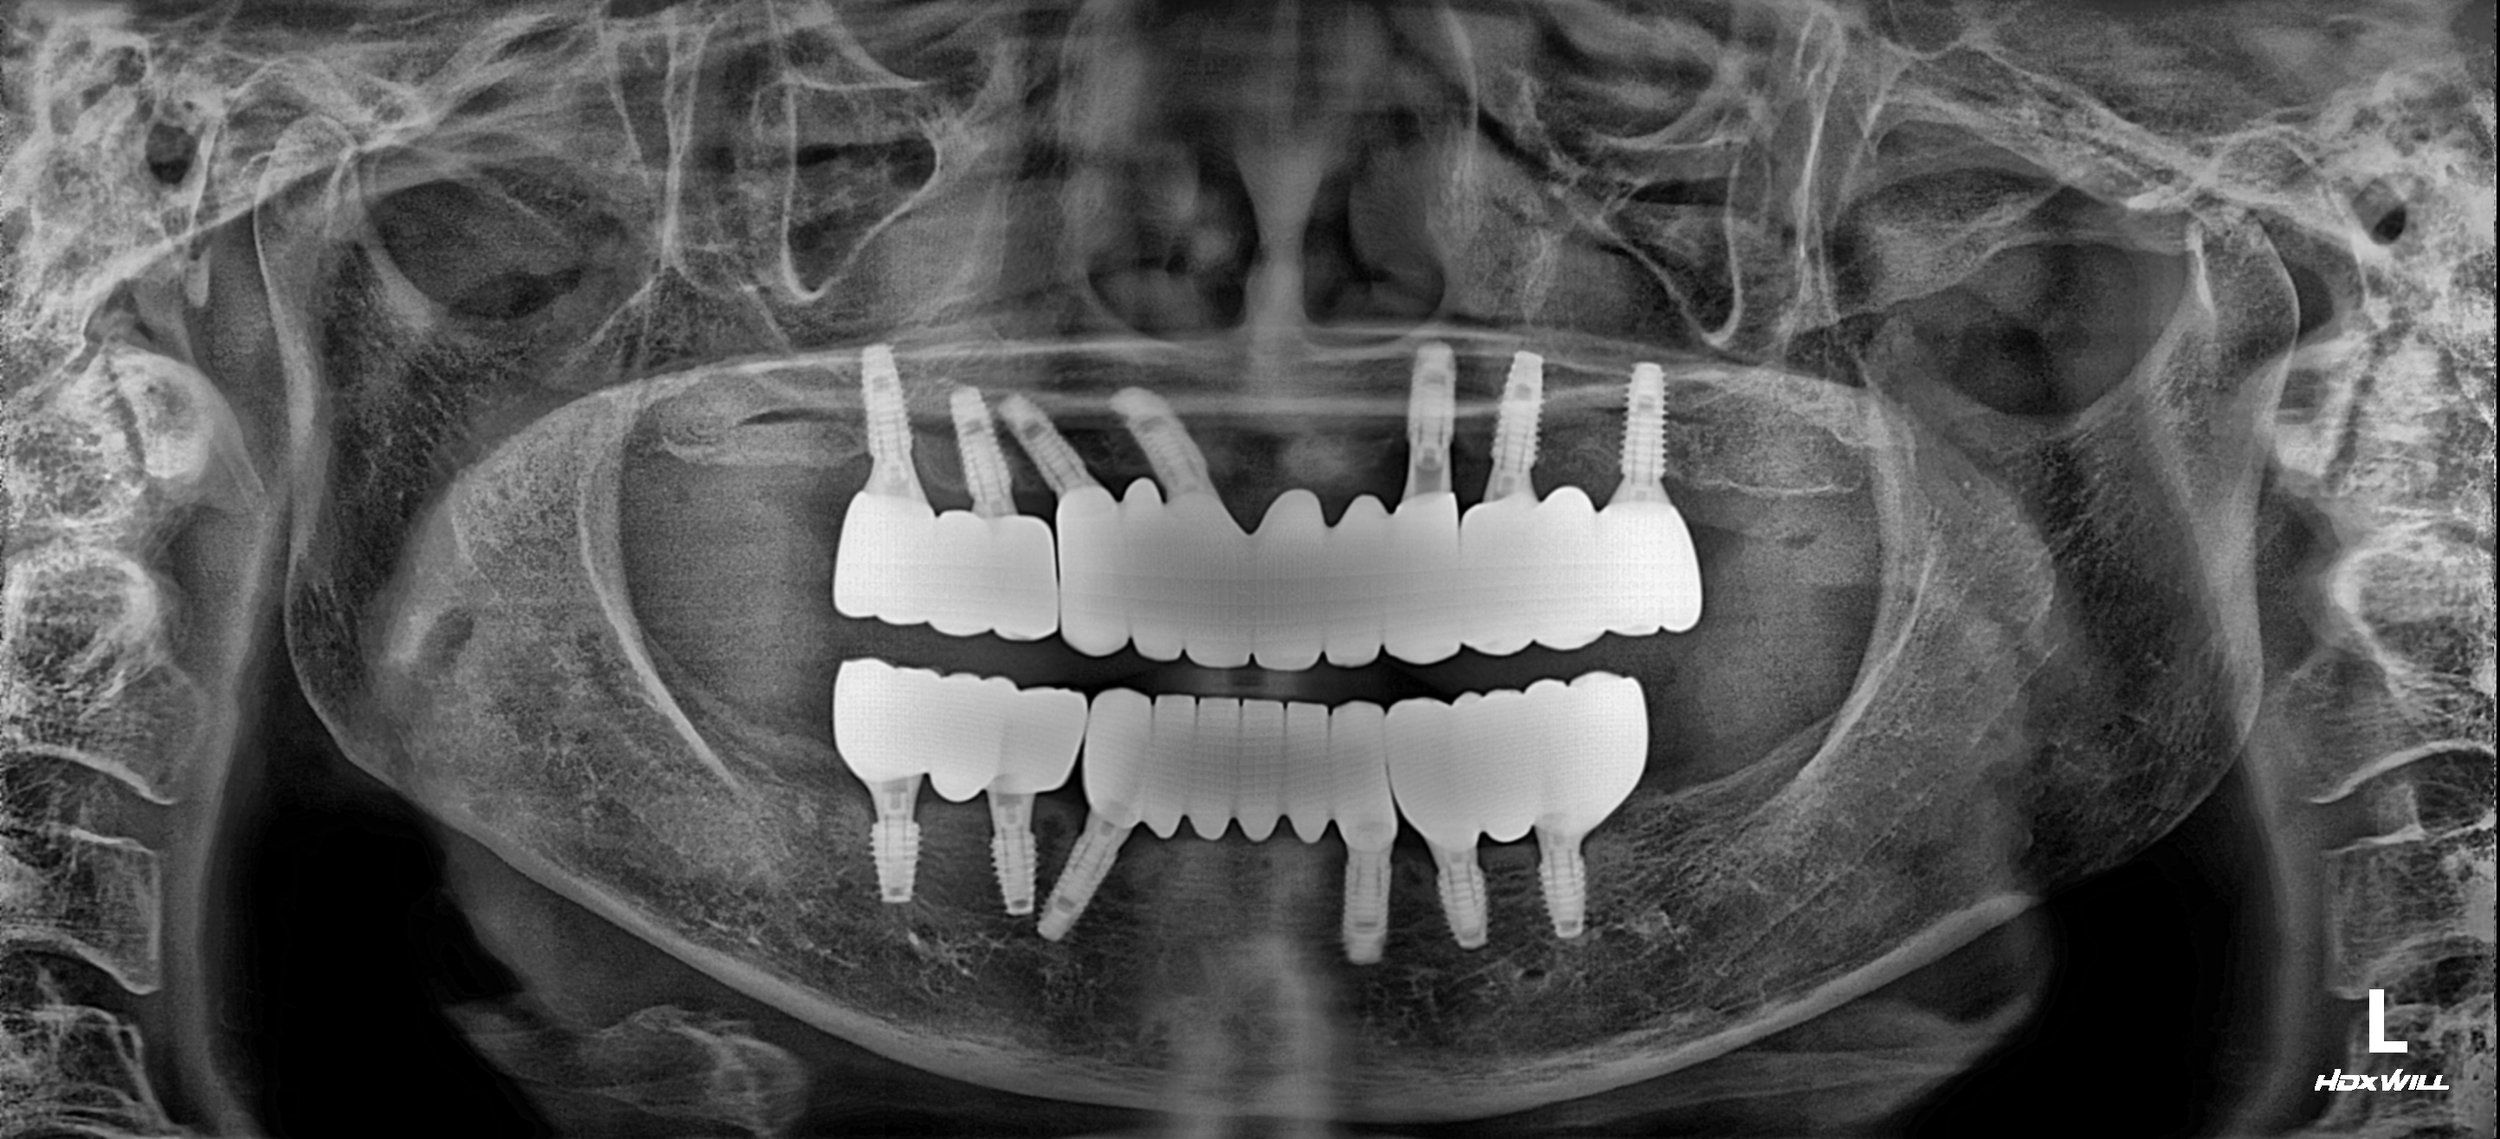

1. Surgical Phase: Comprehensive extractions were followed by the strategic placement of dental implants in both arches. In areas of severe bone loss, guided bone regeneration was utilized to ensure adequate primary stability and long-term integration.

2. Segmented Prosthetic Philosophy: While a one-piece "Full-Arch" bridge was a viable option, a 3-segment design was intentionally chosen for this case. By dividing the arch into smaller segments, we provided several critical advantages:

4. Final Delivery: High-precision zirconia bridges were delivered in the segmented configuration. The result is a functional, stable, and highly aesthetic outcome that the patient can confidently maintain for years to come.

3. VDO Stabilization: The patient’s occlusal height was restored, providing necessary support for the facial tissues and restoring masticatory power.